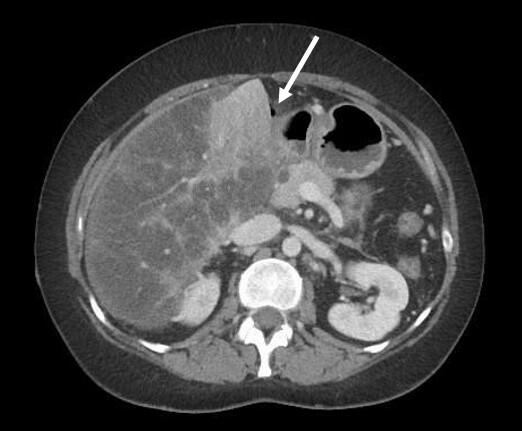

Vital parameters on admission were normal (heart rate 96/min., blood pressure 134/78 mmHg, respiratory rate <22/Min.) the quick Sequential Organ Failure Assessment (qSOFA) score was zero. On physical examination, the abdomen was tender with distension and rebound tenderness in all quadrants. Initial laboratory results showed a mild leucocytosis (10.3G/l) and mildly elevated CRP (30mg/l); elevated liver enzymes (AST 223 U/l, ALT 74U/l, ALP 245U/l, GGT 789 U/l, Bilirubin 51µmol/l), elevated lactate levels (6.9mmol/l) and a decreased factor V (0.50) indicated an acute liver failure. There was a moderate amount of free fluid on ultrasound examination. A CT-scan of the abdomen was performed (Figure 1).

The intravenous-contrast-enhanced CT-scan shows an intestinal perforation with free air around the liver and the gastric antrum, highly suspicious for a perforation of the upper gastrointestinal tract. Ascites, extensive hypodense areas of the liver and spontaneous porto-systemic shunts including esophageal and umbilical varices indicate liver cirrhosis with portal hypertension.